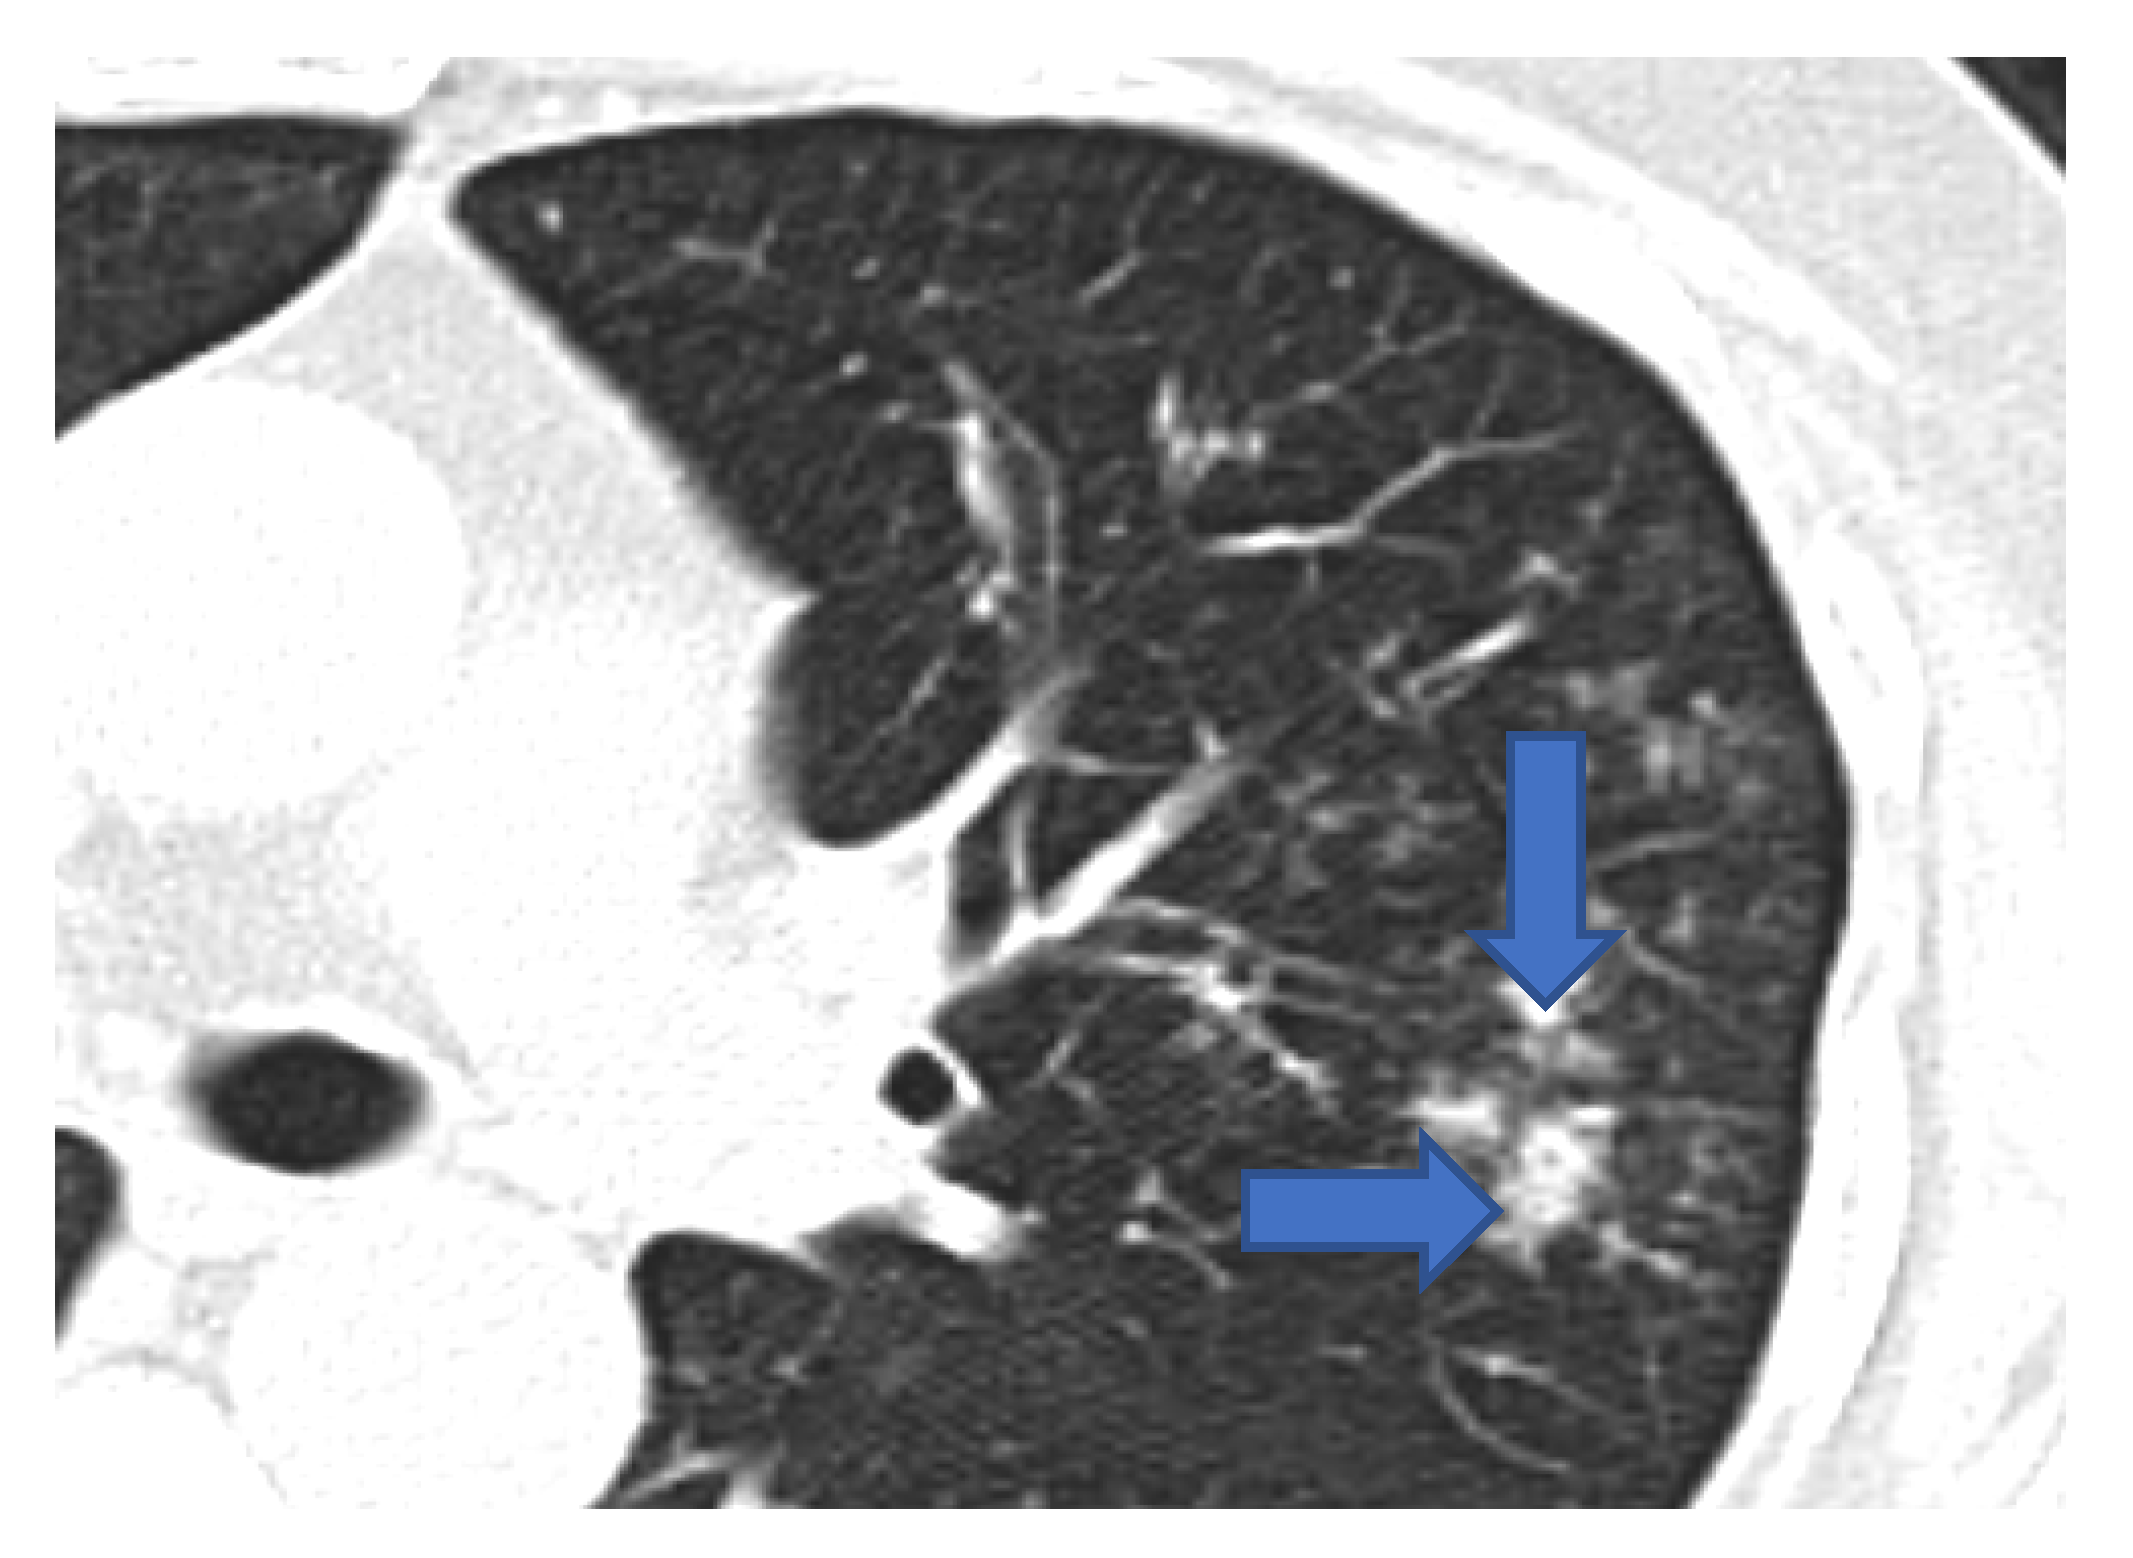

5.1. Role of Diagnostic Imaging

Diagnostic imaging is vital for early detection of invasive mucormycosis in patients with clinical suspicion. Certain distinguishing features of the lung parenchyma on a CT scan of the chest in patients with PM include multiple pulmonary nodules, often pleural-based, presence of lung cavitations and effusions (Figure 1, Figure 2, Figure 3 and Figure 4) [23]. The ‘reverse halo sign’ (central ground glass opacity surrounded by dense consolidation) is highly appreciated, mainly in neutropenic leukemic hosts. In a recent systematic review of CT findings in 16 patients with proven CAPM, consolidation and cavitation were seen in 11 (69%) patients, pleural effusion in 7 (47%), pneumothorax and nodules in 3 (19%) and ‘reverse halo sign’ and pulmonary embolism was seen in 2 (13%) patients [24]. Previously, Nam et al. reported that in hematologic patients, while consolidation and nodules are seen earlier in the disease process, central necrosis, cavitation and the air crescent sign are late findings [25]. This would suggest that CAPM is either under-diagnosed due to lack of differentiation from other fungal, including aspergillosis or bacterial pneumonias, or is diagnosed much later in the illness.

Figure 3. Multiple small nodules (blue arrows). Few show ‘tree in bud pattern’ in left lung parenchyma.